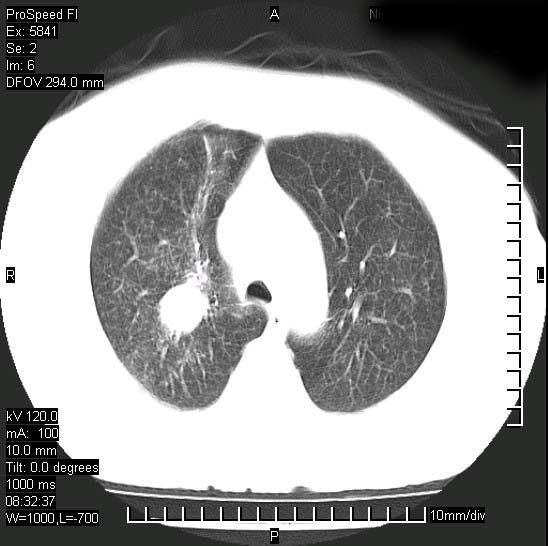

胸痛,咳嗽,气短一周,无发热。右上肺见一结节灶,边缘刺角,内见多个小钙化结节。考虑结核球?肿瘤? 余无异常没有上传。

考虑右肺上叶继发性肺结核,结核球形成。

胸膜是受侵的,考虑感染,结核球可能性大

考虑结核球,并胸膜局限性增厚!!